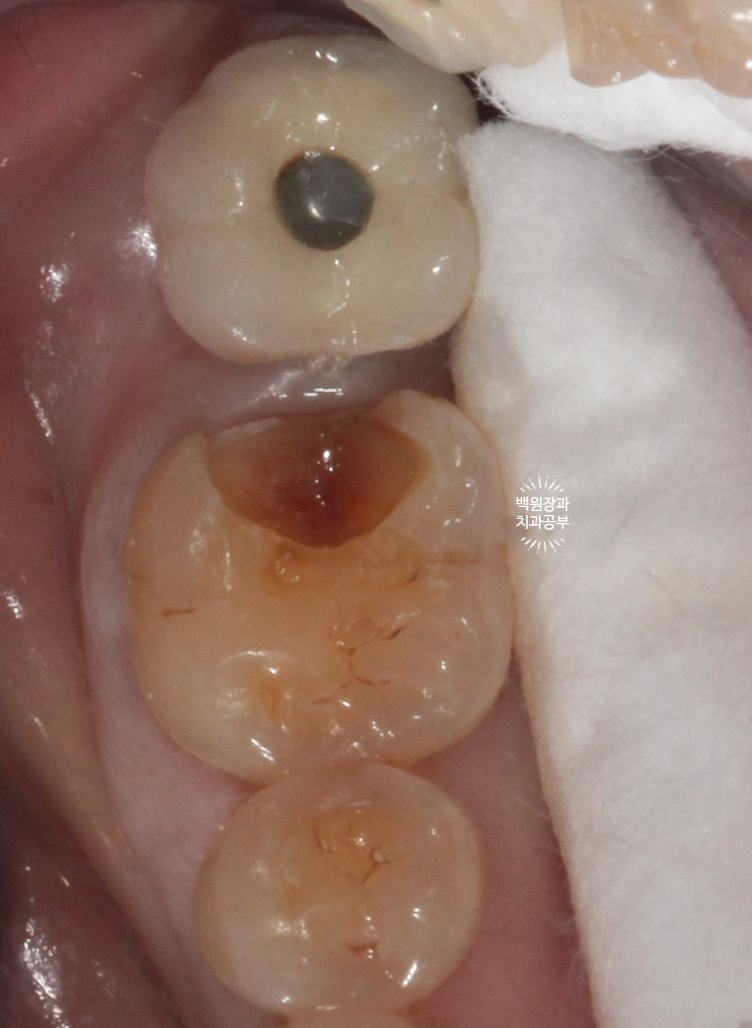

너무 깊었기 때문에 치수를 진정시킬 수 있을 glass ionomer를 base로 사용하여 이장해 주었습니다.

쉽게 얘기하면, 신경이 노출되진 않았지만 너무 가까우므로 단열재를 설치해 주었다! 정도로 이해해주세요.

모양을 비교적 단정하게 정리해 주어 보았습니다.

남은 빈 공간을 단단한 레진을 사용하여 채워줍니다.

레진 코어라고 해요!

보여드리는 치아 같은 경우 기존에 골드인레이가 꽤나 크게 설치되어 있는 상태였는데요,

제거된 골드인레이의 빈 공간 & 2차 충치가 있어 비어있는 공간이 상당히 컸기 때문에

지르코니아 크라운으로 치료계획을 세웠었습니다.